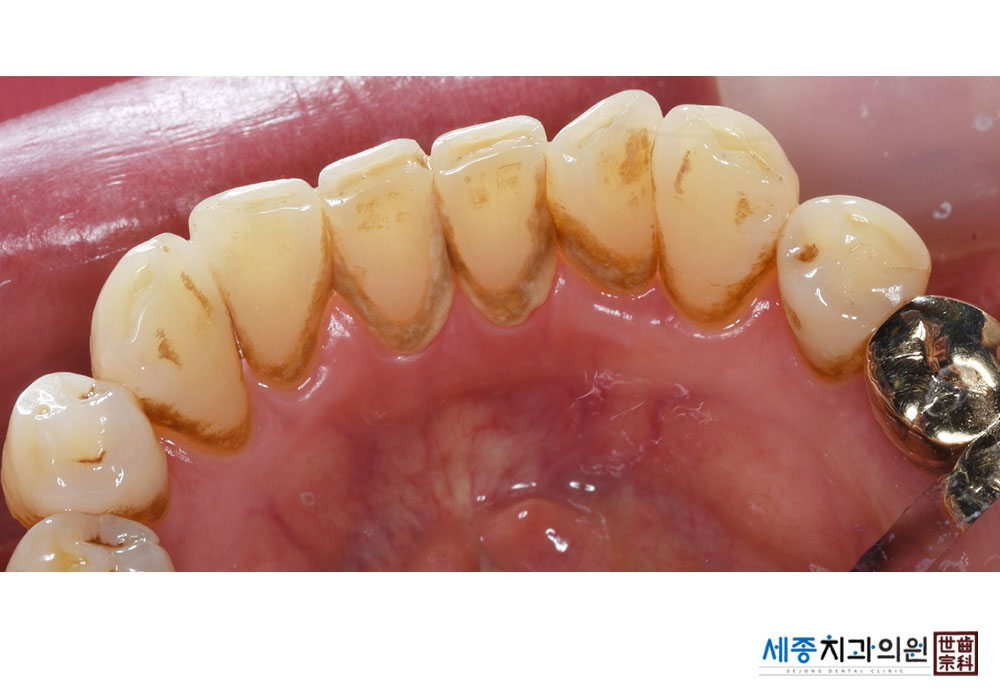

[스케일링] 치주질환 예방 스케일링

치료후 : 2023-02-13

가글마취&저주파 스켈러를 사용한 스케일링